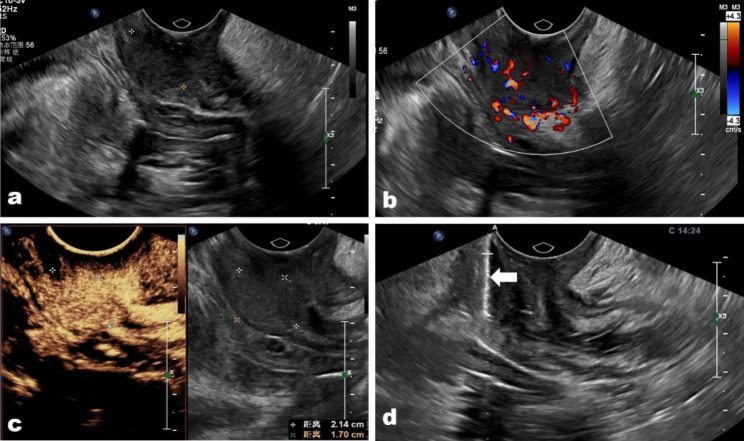

Fig. 3.

(a) A cervix metastasis squamous carcinoma located in the anal tube in a 43-year-old woman was misdiagnosed. (b) The tumor showed abundant vascular on color Doppler image; (c) the tumor presented hyper-enhanced on contrast-enhanced condition, and there was no necrosis area in the tumor. (d) The biopsy needle (arrow) passes through the tumor center to acquire biopsy samples